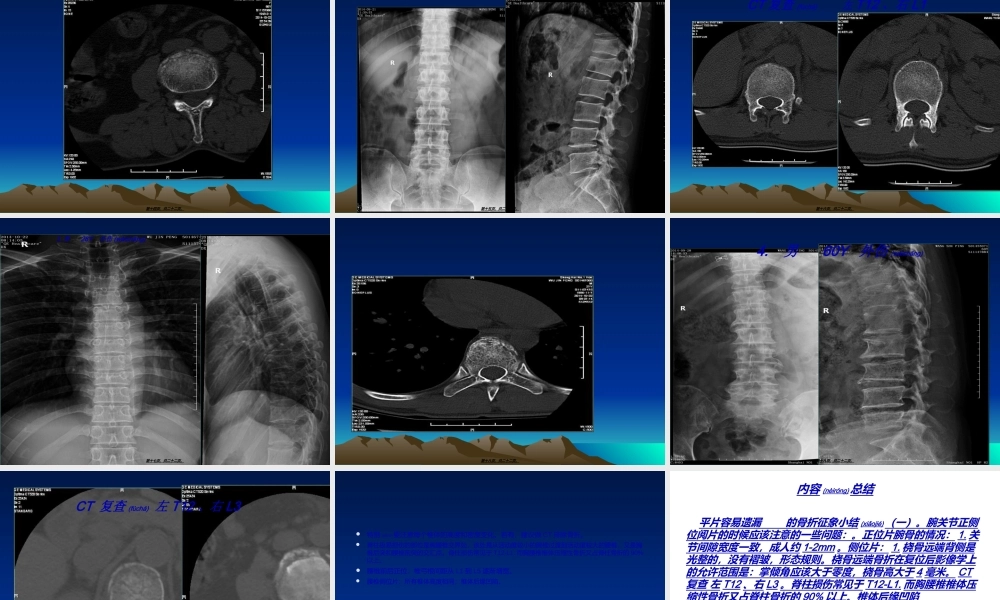

平片容易遗漏的骨折(gǔzhé)征象小结(一)鲁伦博14-10-26第一页,共二十二页。•一、腕关节正侧位1.女66岁外伤(wàishāng)第二页,共二十二页。腕关节CT•第三页,共二十二页。2.男19Y外伤(wàishāng)第四页,共二十二页。•第五页,共二十二页。•第六页,共二十二页。5女55Y外伤(wàishāng)第七页,共二十二页。第八页,共二十二页。第九页,共二十二页。(ráogǔ)•是指骨折发生在桡骨下端(xiàduān)2-3cm范围内的骨松质部位。•主要为三种:a.colles’骨折。患者掌侧着地,常伴有远侧骨折断端向背侧倾斜,掌倾角减少或成负角。典型者伤手呈银叉畸形b.Smith骨折。又称反colles’骨折。患者手背着地,c.Barton骨折。腕关节半脱位伴随桡骨远端骨折。也即桡骨远端骨折累及桡腕关节面。第十页,共二十二页。正侧位阅片的时候应该注意的一些问题:腕骨的情况:1.关节间隙宽度一致,成人约1-2mm骨骼表面相互平行或一致。的关节间隙变窄可能是由于X线投照体位的原因,或者是退行性改变,很为外伤所致。的关节间隙增宽可能是外伤所致。片:1.桡骨远端背侧是光整的,没有褶皱,形态规则。远端、月骨和头状骨相互构成关节并位于一条直线上。(主要是应用于ěnduàn)月骨回旋性脱位和月骨周围性后脱位,前者时月骨凹空虚,桡骨和头上,后者时桡骨和月骨保持在一条直线上,头状骨向后移位,和月骨直线上。)关节面有一向掌侧倾斜的角度,倾斜角平均为10°。第十一页,共二十二页。(正位X线片上的桡骨茎突上端和尺骨茎突上端分别做一条水平线,两线高度之差即为桡骨高,在11至12mm第十二页,共二十二页。二腰椎(yāozhuī)正侧位1.女66Y外伤(wàishāng)第十三页,共二十二页。第十四页,共二十二页。2.男36Y外伤(wàishāng)第十五页,共二十二页。CT复查(fùchá)左T12、右L1第十六页,共二十二页。3.男28Y外伤(wàishāng)第十七页,共二十二页。第十八页,共二十二页。4.男60Y外伤(wàishāng)第十九页,共二十二页。CT复查(fùchá)左T12、右L3第二十页,共二十二页。•特别(tèbié)要注意每个椎体的高度和密度变化。若有,建议做CT排除骨折。•脊柱极易损伤的部位是胸腰椎交界处,该处是从活动度较小的胸椎过渡到活动度较大的腰椎,又是胸椎后突和腰椎前突的交汇点。脊柱损伤常见于T12-L1.而胸腰椎椎体压缩性骨折又占脊柱骨折的90%以上。•腰椎前后正位:椎弓根间距从L1到L5逐渐增宽。•腰椎侧位片:所有椎体高度相同;椎体后缘凹陷。第二十一页...